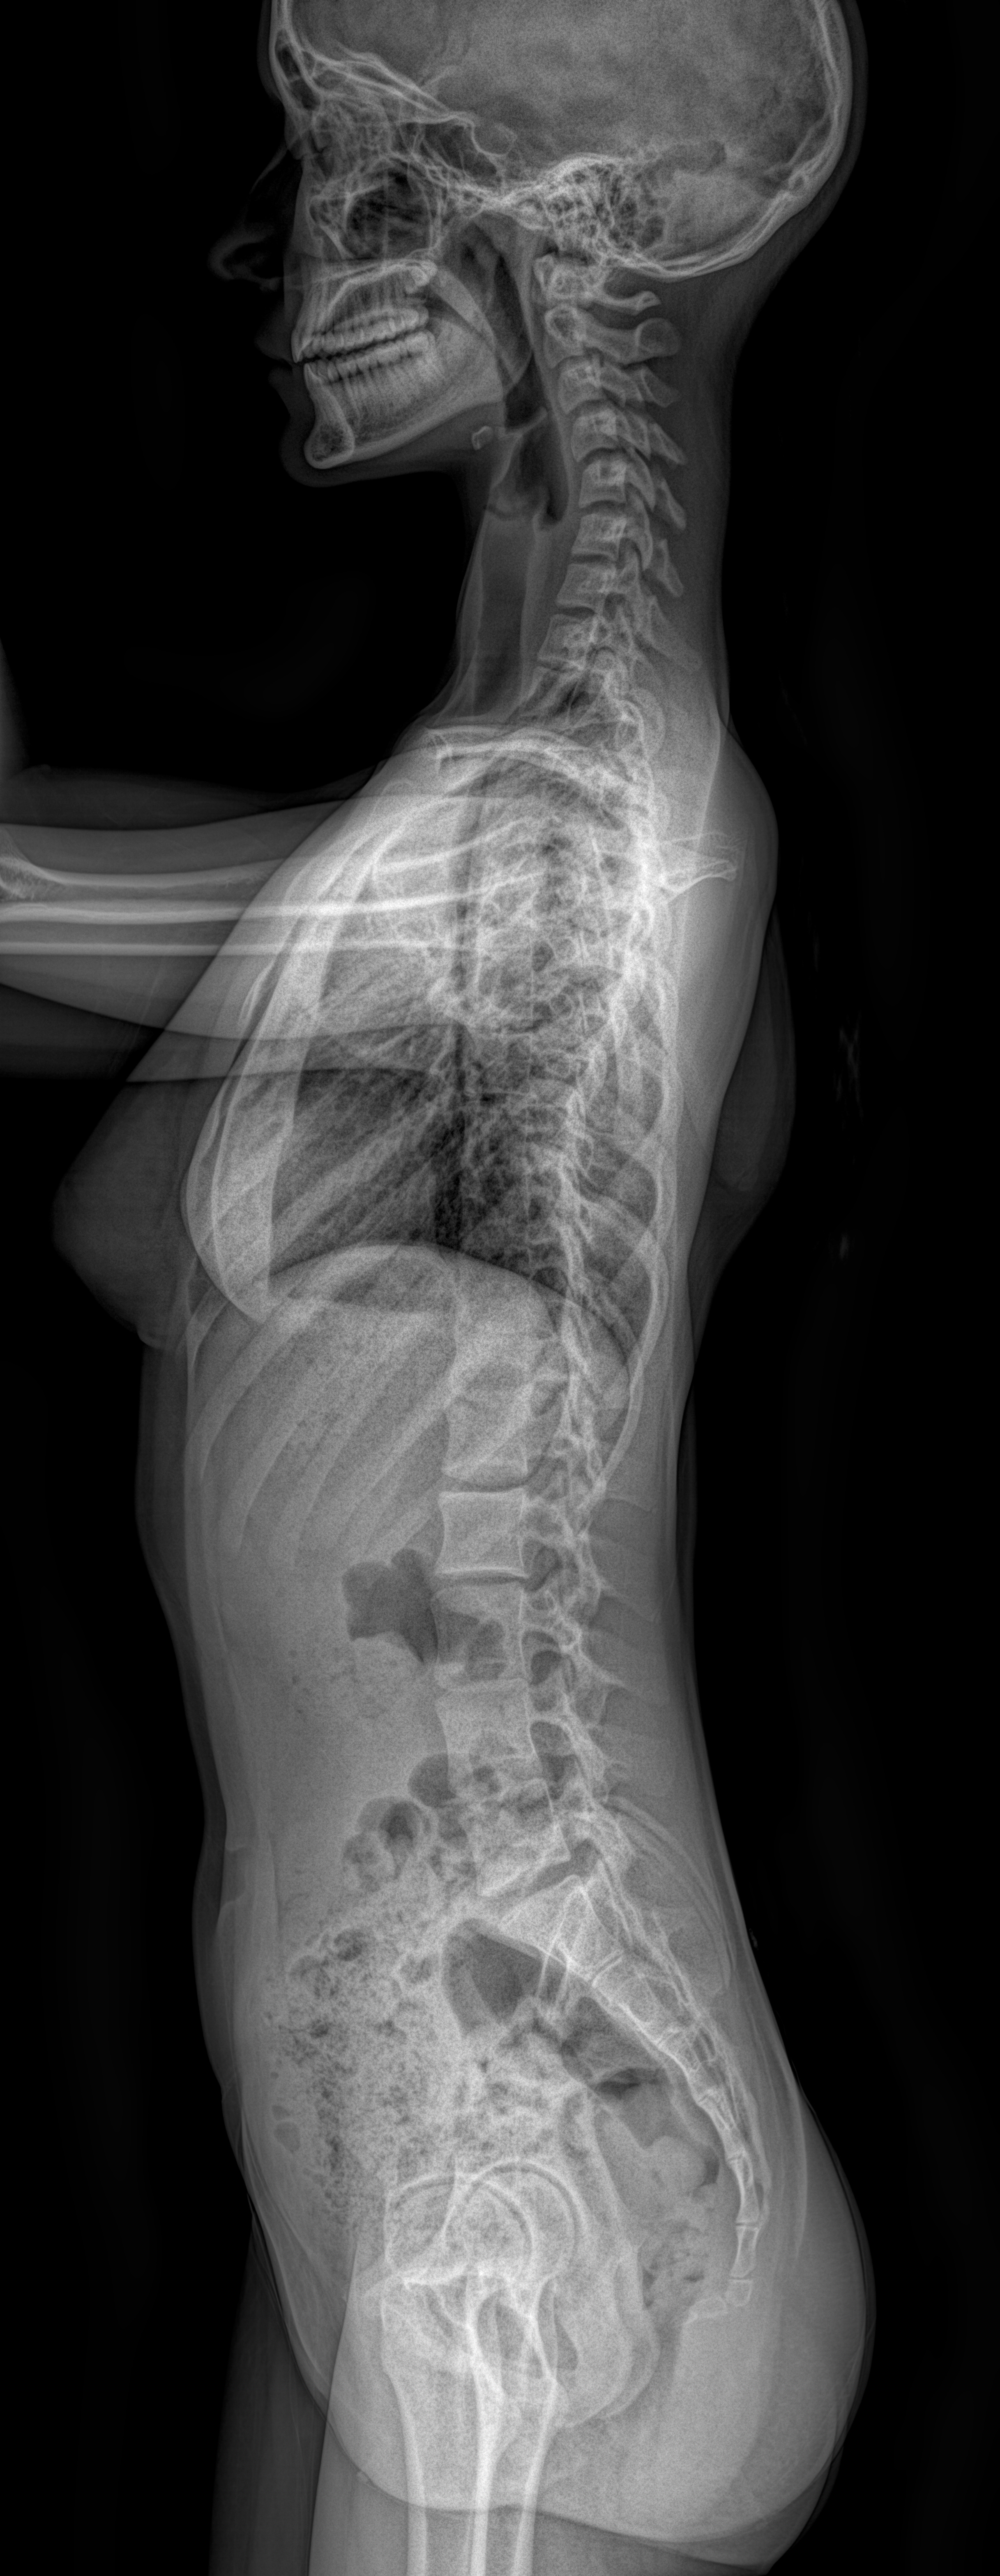

EOS skolyoz grafisi, omurga eğriliklerinin hassas ölçümlerle görüntülenmesine imkan tanır. Merkezimizdeki EOS cihazı, skolyoz takiplerinde güvenli ve tekrarlanabilir sonuçlar sağlar.